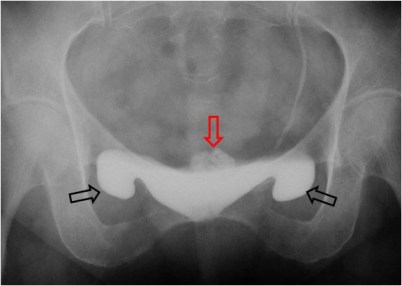

SIGNO DE LAS OREJAS VESICALES

Variante de la normalidad visible hasta en un 10 % de niños, en la urografía intravenosa. Consiste en la presencia de prolongaciones laterales de la vejiga (flechas negras), que desaparecen con la distensión vesical. Corresponden a la herniación extraperitoneal, normalmente bilateral, de la vejiga que ocurre en niños menores de un año y que después normalmente desaparece.

En este caso se trata de un varón adulto en el que persisten estas prolongaciones.

El paciente también tiene calcificaciones prostáticas (flecha roja).